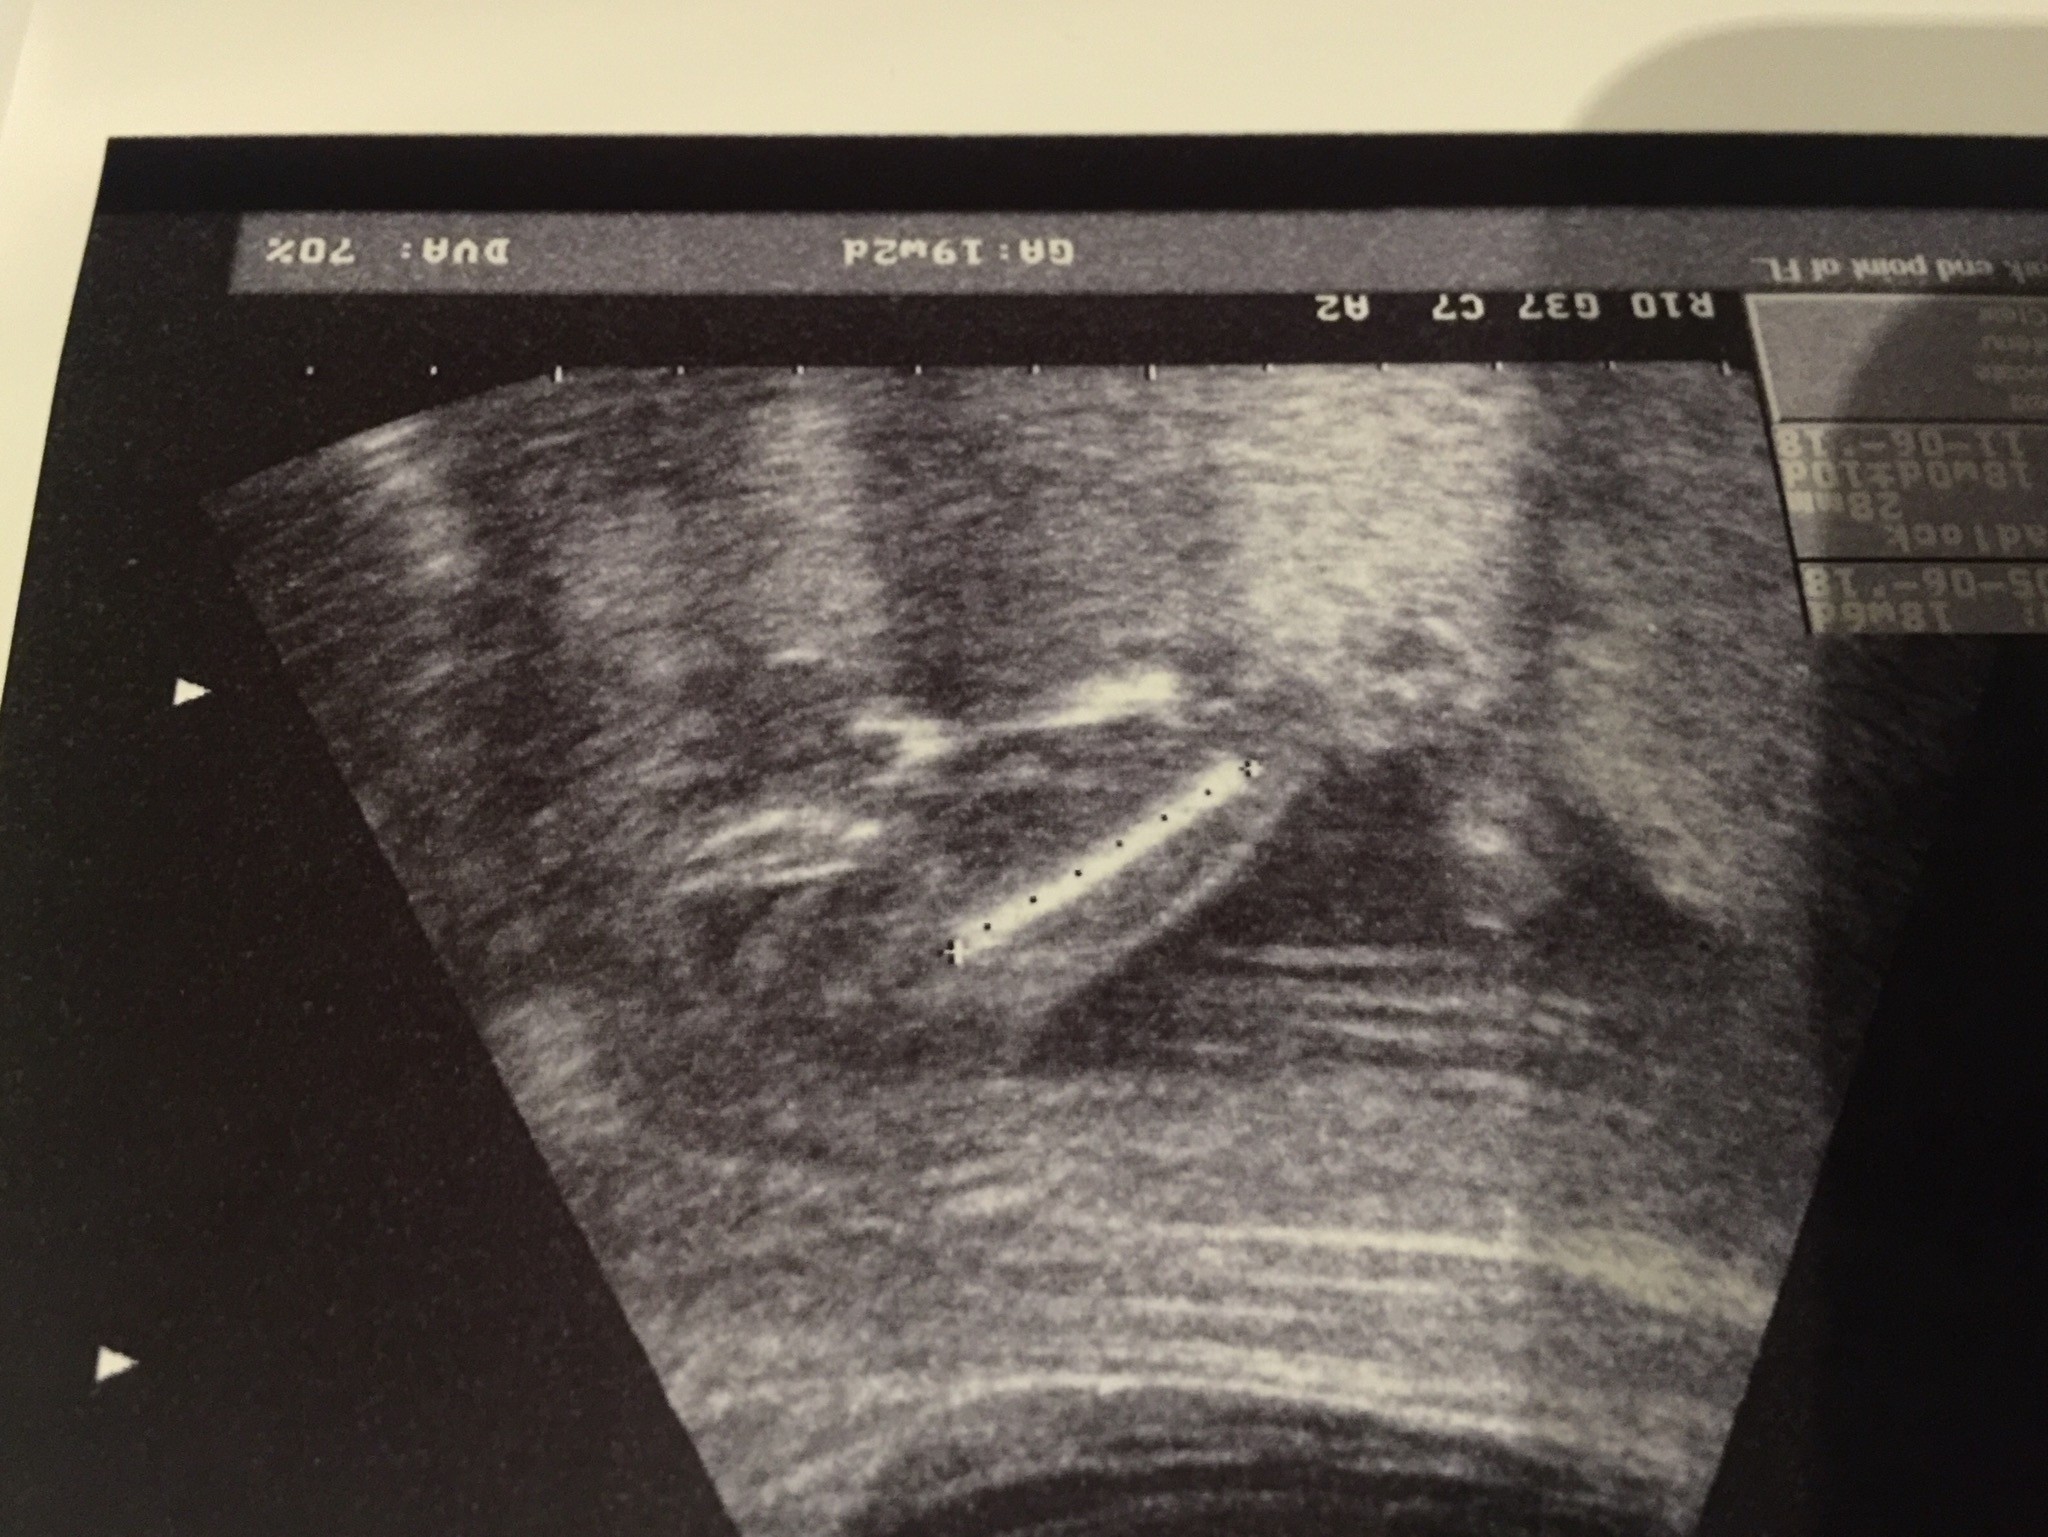

Witam w 19 tygodniu ciąży dowiedziałam się ze będę miała dziewczynkę w 20 tyg okazało się jednak , że to chłopak. Sama już nie wiem bo na jednym usg widać na pewno dziewuche a na drugim chłopca. Może to pempowina ?? Może ktoś mi pomoże rozwiązać ta zagadkę

W poniedziałek miałam połówkowe lekarz powiedział na 90% chłopczyk jedno zdjęcie mam od dołu drugie od przodu ale z przodu nic nie odstaje :p